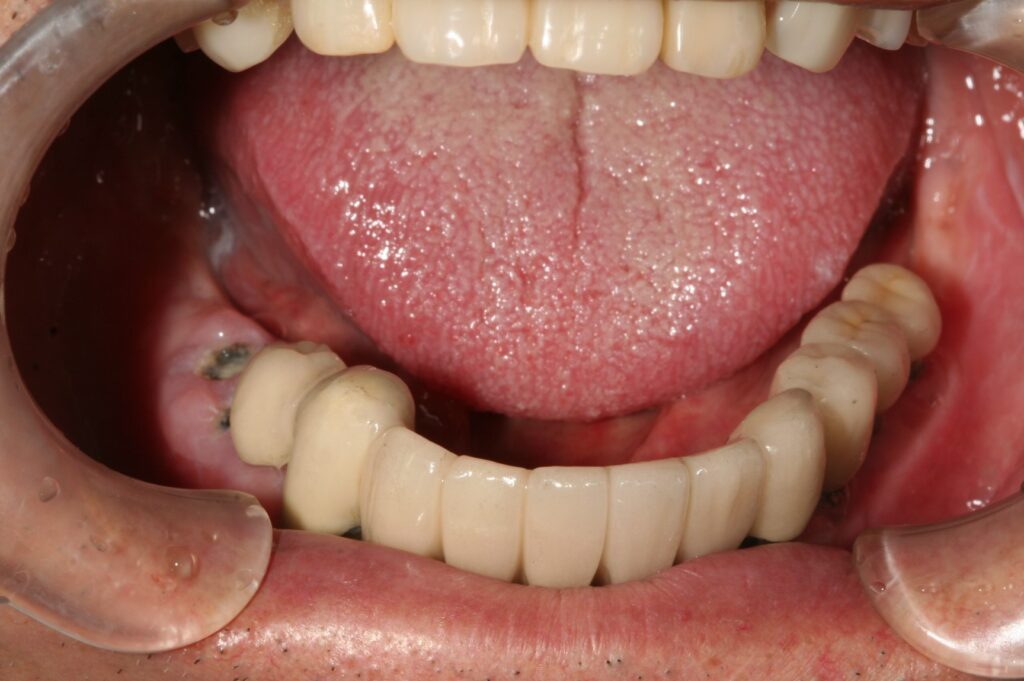

インプラント 2018.06.5 症例紹介 歯が無い部分は取り外しの入れ歯をしてありましたが、固いものが噛めないということでインプラントをし固定式の被せ物にしました。 症例紹介 ランニング前の記事 歯 を守る次の記事